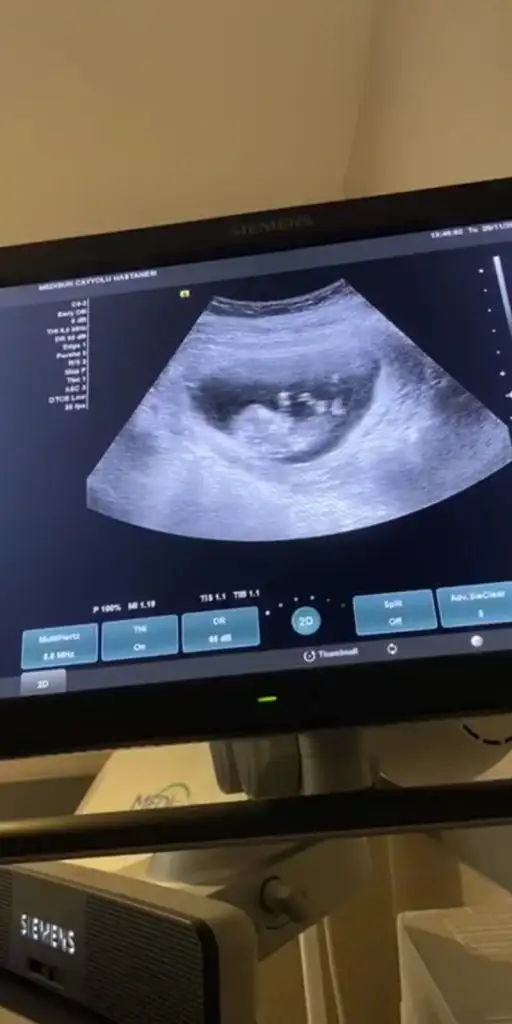

Şekil almamış kız olabilirkizlar buna da yorum yapar misiniz. 10

hafta icinde

şekil almamış derken. kötü birşey miŞekil almamış kız olabilir

Hayır ne den kötü olsun erkek bebekleri de uzuvlar daha net belli oluyo bu haftalarda o yüzden dedim kız olabilir diyeşekil almamış derken. kötü birşey mi

Bilmiyordum ondan sordum teşekkür ederim.Hayır ne den kötü olsun erkek bebekleri de uzuvlar daha net belli oluyo bu haftalarda o yüzden dedim kız olabilir diye